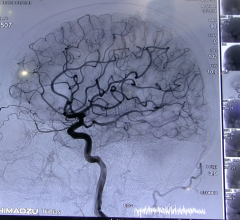

Stroke is the fifth leading cause of death in the United States, responsible for more than 140,000 deaths in some of the ...

Medical robotics company Neural Analytics Inc. announced that it received CE Mark for its NeuralBot System, a robotic assistance technology which automatically adjusts orientation and position of its ultrasound products under the guidance of a healthcare professional. The system has also received 510(k) clearance from the U.S. Food and Drug Administration (FDA). When used with its previously cleared Lucid M1 Transcranial Doppler Ultrasound System, it can assist clinicians to non-invasively monitor a patient’s brain blood flow characteristics and can provide information to diagnose a variety of neurological disorders.

Dictum Health Inc., creators of the Virtual Exam Room (VER) telehealth technology, announced the release of their Care Central advanced telestroke module. The module provides neurological images viewing capability for use with the VER to reduce door-to-needle time, improve patient outcomes and lower costs.